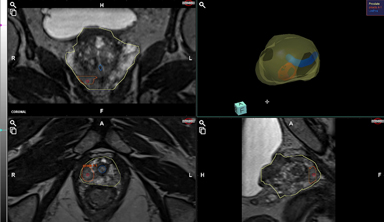

Needle Pre-planning

Systematic Needles Pre-planning

(with Anatomical Biopsy Model)